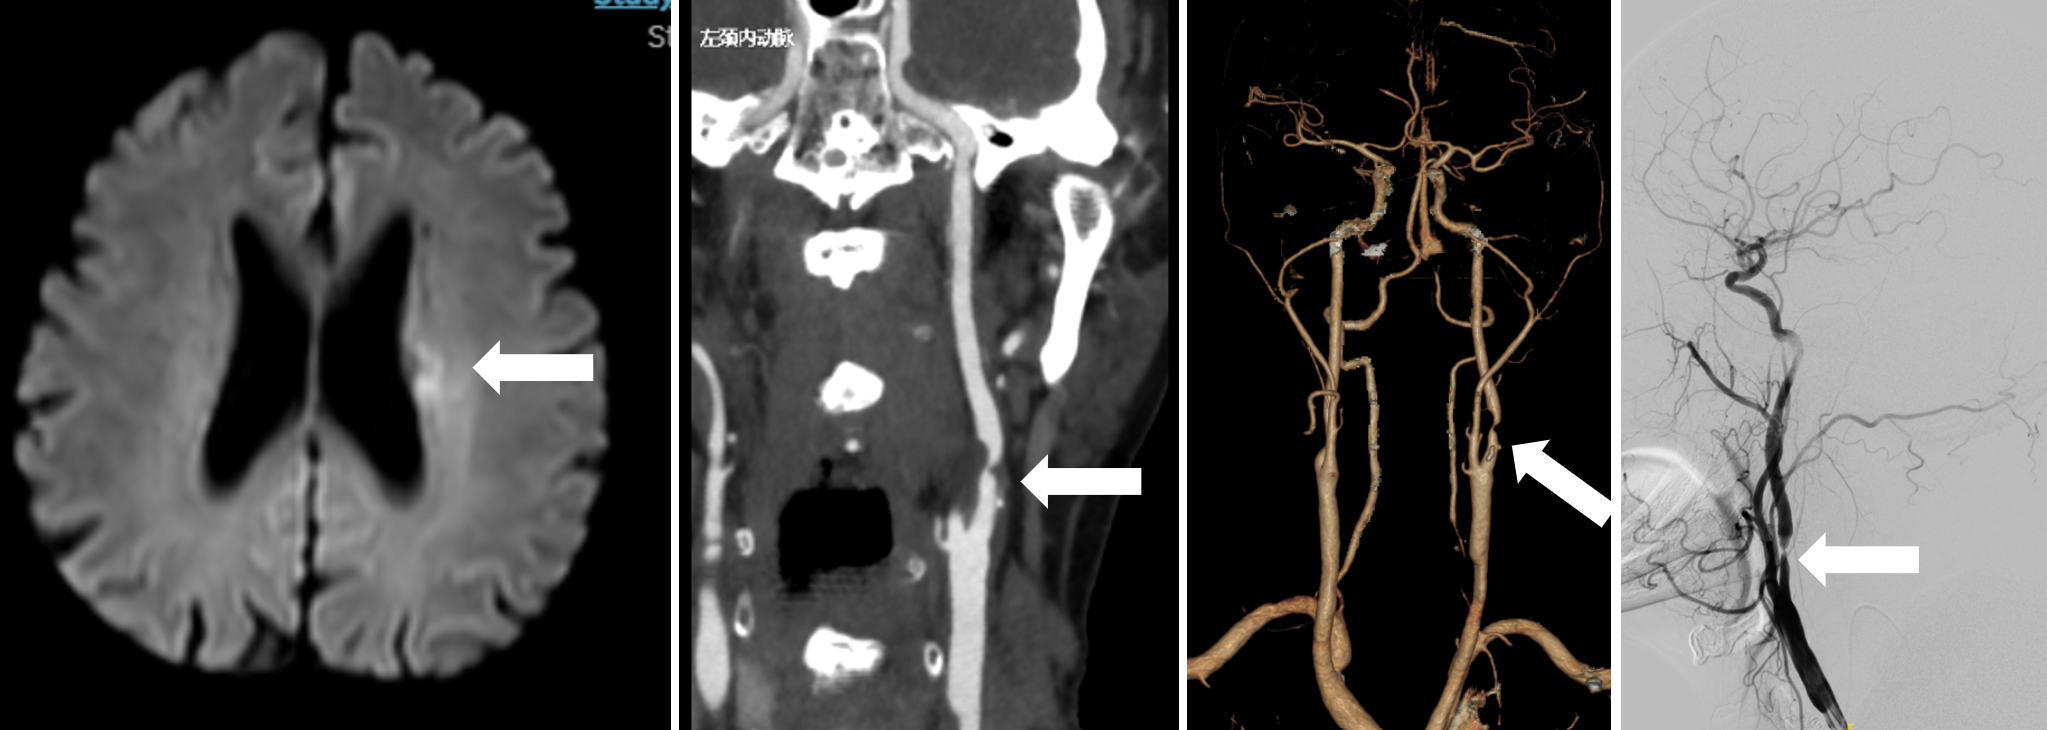

患者为因左侧脑梗死入院。经检查确诊为侧颈内动脉起始部重度狭窄伴不稳定斑块形成,导致脑梗死。王也副主任医师介绍,患者的病变部位狭窄程度严重,且斑块性质不稳定,传统的血管造影难以准确判断斑块的具体情况,增加了手术风险。而OCT成像技术的应用,为手术带来了转机。

评估患者术前术中影像,可见左侧半球亚急性脑梗死灶,左侧颈内动脉起始部重度狭窄

分析患者左颈动脉斑块的高分辨率核磁特点,结合OCT影像可见斑块不稳定,呈现薄纤维帽易破裂型